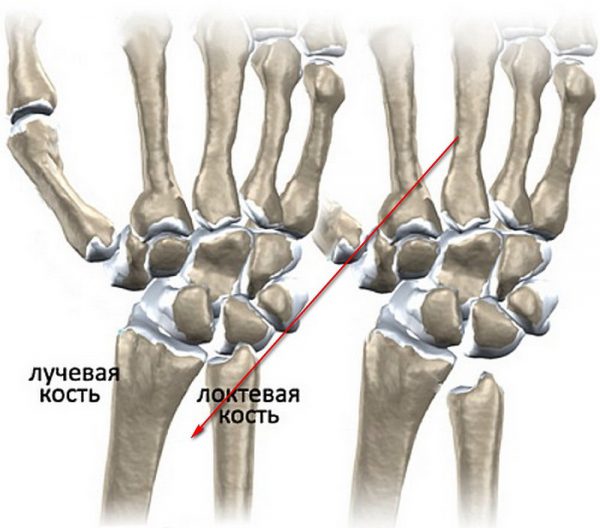

Лучезапястный сустав принадлежит к числу сложных и имеет больше двух суставных поверхностей. Он отличается от большинства других сочленений, ведь в нем участвует 5 костей (а не 2-3, как, например, в коленном или межфаланговых суставах). Кроме того, лучезапястный сустав имеет две оси вращения, а не одну. Это позволяет двигать кистью во всех направлениях и даже вращать ею по кругу.

Хрупкий лучезапястный сустав находится между кистью и предплечьем и, в силу расположения, подвержен травмам (например, при падении). В повседневной жизни он испытывает меньшую функциональную нагрузку, чем, скажем, коленный сустав, но и суставная капсула у него тоньше. А потому сочленение уязвимо даже перед незначительными повреждениями.